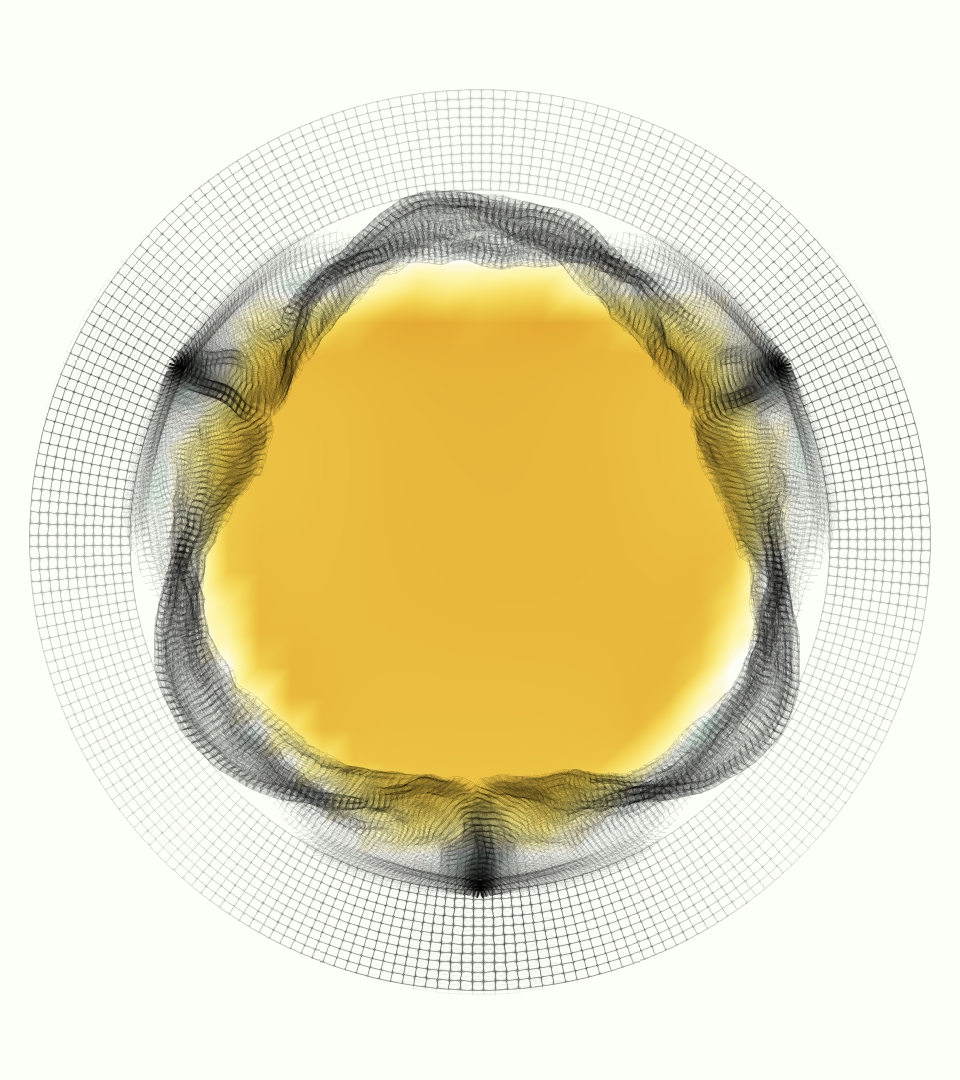

The gross morphology of the model valve that emerged from this process is shown in Figure 4. The free edge was 2.87 cm, corresponding to 3.3 cm in the predicted loaded configuration. After the pinching the leaflets together at the commissures, this left approximately 2.1 cm of free edge rest length per leaflet free to move independently of the other leaflets, within measurement error of ±0.1 cm from the free edge length of 2.2 cm measured on the prostheses. The leaflet rest height was 0.94 cm corresponding to a predicted loaded height of 1.44 cm. The measured leaflet height of 1.3 cm is nearly the predicted loaded height of 1.44 cm, which may be because the leaflets are so compliant in the radial direction, that pulling them flat to measure them achieved substantial stretches. The fiber orientation of the model runs from commissure to commissure and qualitatively matches experimental observations [38], though direct quantitative comparison is beyond the scope of this work. One minor limitation is that we do not add bending rigidity to the leaflets, beyond what emerges from the thickening process described above, and thus may not accurately capture leaflet flutter or other similar behaviors. Based on the thickness of mm, we estimated the mean tangent modulus at the predicted loaded stretches as dynes/cm2 circumferentially and dynes/cm2 radially. The prosthetic valve tissue is fixed in glutaraldehyde, and literature values for the fully-recruited circumferential tangent modulus of fixed porcine aortic valve tissue vary widely. Based on the experimental measurements of Billiar and Sacks and their constitutive law for valves fixed under 4 mmHg of pressure, we evaluated their constitutive law at the relevant stretches and and estimated the circumferential tangent modulus to be dynes/cm2 [6]. Rousseau et al. reported moduli ranging from to dynes/cm2, depending on the applied preload during fixation [36]. Sung et al. reported moduli ranging from to dynes/cm2, depending on fixation pressure [43]. Thus our estimated tangent modulus falls within the range of existing studies, so we considered our resultant modulus in good agreement given the complexity of the steps involved, phenomenological nature of the constitutive law and uncertainties in experiments. We do not have access to the precise material properties of the prosthetic valve, and further, the only literature we could find on the material properties of a similar prostheses reported the tangent modulus at one particular loading, which did not appear to be at a relevant stretch for comparisons with our model [19]. Thus, our model has material properties in a reasonable range for a fixed aortic valve prostheses (placed in the pulmonary position in our simulations), but it does not directly model the material properties of the prostheses.

We constructed the model vessel for FSI simulations from data from the MRI scans (Figure 4). The signal magnitude of 3D printed model material is distinct from the signal of the fluid in the scans, and we applied a thresholding operation to generate a three-dimensional model of the printed vessel surface. Using the MRI data ensured that the MRI and simulation coordinates were consistent in space and there were no alignment or registration errors. While using the files that generated the 3D printed model would have offered more spatial fidelity, the potential error in flow fields due to any mis-registration would have likely been much more substantial. Using Meshmixer (San Rafael, CA), we smoothed the mesh to remove stair-step effects and removed artifacts from the valve scaffold. We then remeshed to the desired edge length of 0.25 mm and extruded the model 0.25 mm and 0.5 mm to create a three-layer structure. As in the valve, this serves to eliminate the “grid aligned artifact” that can occur with pressure differences across thin membranes in the IB method [16]. Flow extenders of length 1 cm were added to the vessel at the inlet and both outlets to ensure that the normal to the vessel was aligned with the normal of the fluid box at the inlets and outlets. In FSI simulations, the vessel was held in place using target points, stiff springs of zero rest length that connect the current position of each model node to its desired position (Section 3.3). Additional linear springs are placed on each edge in the triangulated model. These springs are not meant to model a particular material and only serve to keep the vessel rigid and stationary throughout the simulation.

The phase-averaged, resampled velocity fields during peak systole and flow rates at each resolution are shown in Figure 10. Despite the limitations discussed above, we observe similar qualitative trends in the flow field at all resolutions. At all resolutions, a jet formed and angled up downstream of the valve orifice, as shown in the sagittal view. The jets showed a triangle-like cross section at with points aligned with the commissures. At cm, the jet appears like a rounded triangle in the opposing orientation, with its points aligned with the center of the leaflets. At cm, the jet is narrower downstream of the commissures, and wider downstream of the leaflets, again with a triangle-like cross section. The area of the jet increased with resolution, as expected given the IB method thickening of the valve structure. The narrowed jets at the two more coarse resolutions show locally elevated velocities relative to the two more fine resolutions. Figure 11 shows the instantaneous velocity fields at each resolution in the same axial and sagittal views. At 0.9 mm, the sagittal view shows a qualitatively different jet than at finer resolutions, with regions of lower velocity farther from the vessel wall, indicating insufficient resolution. At 0.9 and 0.68 mm, the jet is visibly narrowed compared to higher resolutions. While some features are similar at these two coarse resolutions, we conclude that the narrower jets indicate these simulations are under-resolved. Flows in the three finest resolutions, 0.45, 0.34 and 0.28 mm. appeared qualitatively similar, with slightly more fine structure detail in both the axial and sagittal views present at the edges of the jet. The jets in the axial views all showed a similar triangle-like cross section, slightly narrower downstream of the commissures, as in the phase-averaged fields. In both the phase-averaged and instantaneous fields, the three finest resolutions appear sufficiently similar that the conclusions of this study would be identical with any of these resolutions.

| axial | axial | axial | sagittal | |

| = 0 cm | = 0.625 cm | = 1.25 cm | ||

0.9 mm |

|

|

0.68 mm |

|

|

0.45 mm |

|

|

0.33 mm |

|

|

0.28 mm |

|

|